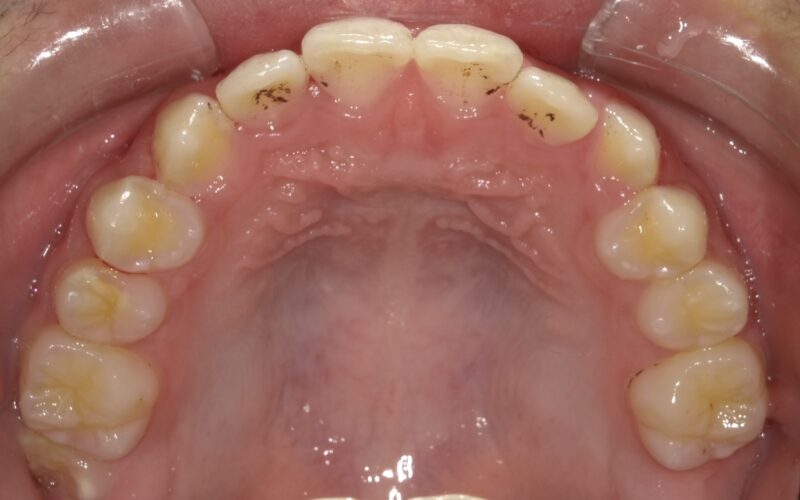

■ 治療経過(約3年間)

・上顎の幅径の改善

・前歯部の反対咬合の解消

・上下顎の前後的バランスの改善

成長を利用しながら、無理のない矯正を行うことで、

永久歯が自然に並ぶ環境を整えることができました。

■ 治療結果

3年の経過で反対咬合は改善し、

現在は安定した咬合関係を維持しています。

現時点では、

本格的なワイヤー矯正(2期治療)の必要性は低いと判断しています。